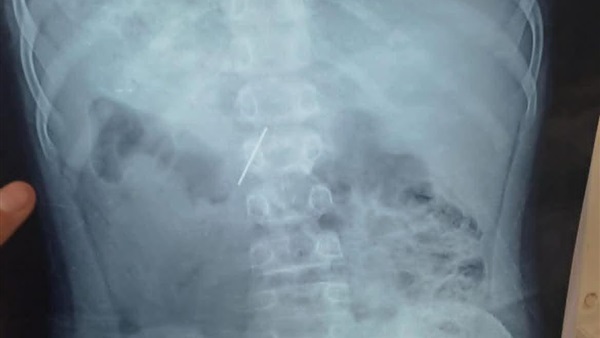

نجح قسم جراحة الأطفال بمستشفى الأطفال التخصصي ببنها، في استخراج مسمار دباسة كراسة اخترق جدار بطن طفل واستقر داخل التجويف البطني، بعد تدخّل جراحي متقدّم جمع بين المنظار الجراحي وجهاز السي أرم لتحديد الموقع بدقة متناهية.

وصل الطفل إلى المستشفى وهو يعاني ألمًا شديدًا وقلقًا أسرته، وكشفت الفحوصات الأولية وجود جسم غريب حاد داخل البطن.

قرار الفريق كان حاسمًا: استئصال المسمار بأسرع وأأمن طريقة ممكنة لتفادي أي مضاعفات قد تهدد حياة المريض.

قاد العملية فريق متميز بقيادة الدكتور محمد متولي رئيس قسم جراحة الأطفال، وبمشاركة د. وليد محمد استشاري جراحة الأطفال ود. محمود ممدوح نائب قسم جراحة الأطفال، تم توظيف المنظار الجراحي لتقليل آثار الجراحة والشفاء السريع، فيما لعب جهاز السي أرم دور الخريطة الحية لتحديد موقع المسمار بدقة مدهشة، ما حول العملية إلى مزيج من مهارة الجراح وذكاء الأجهزة.